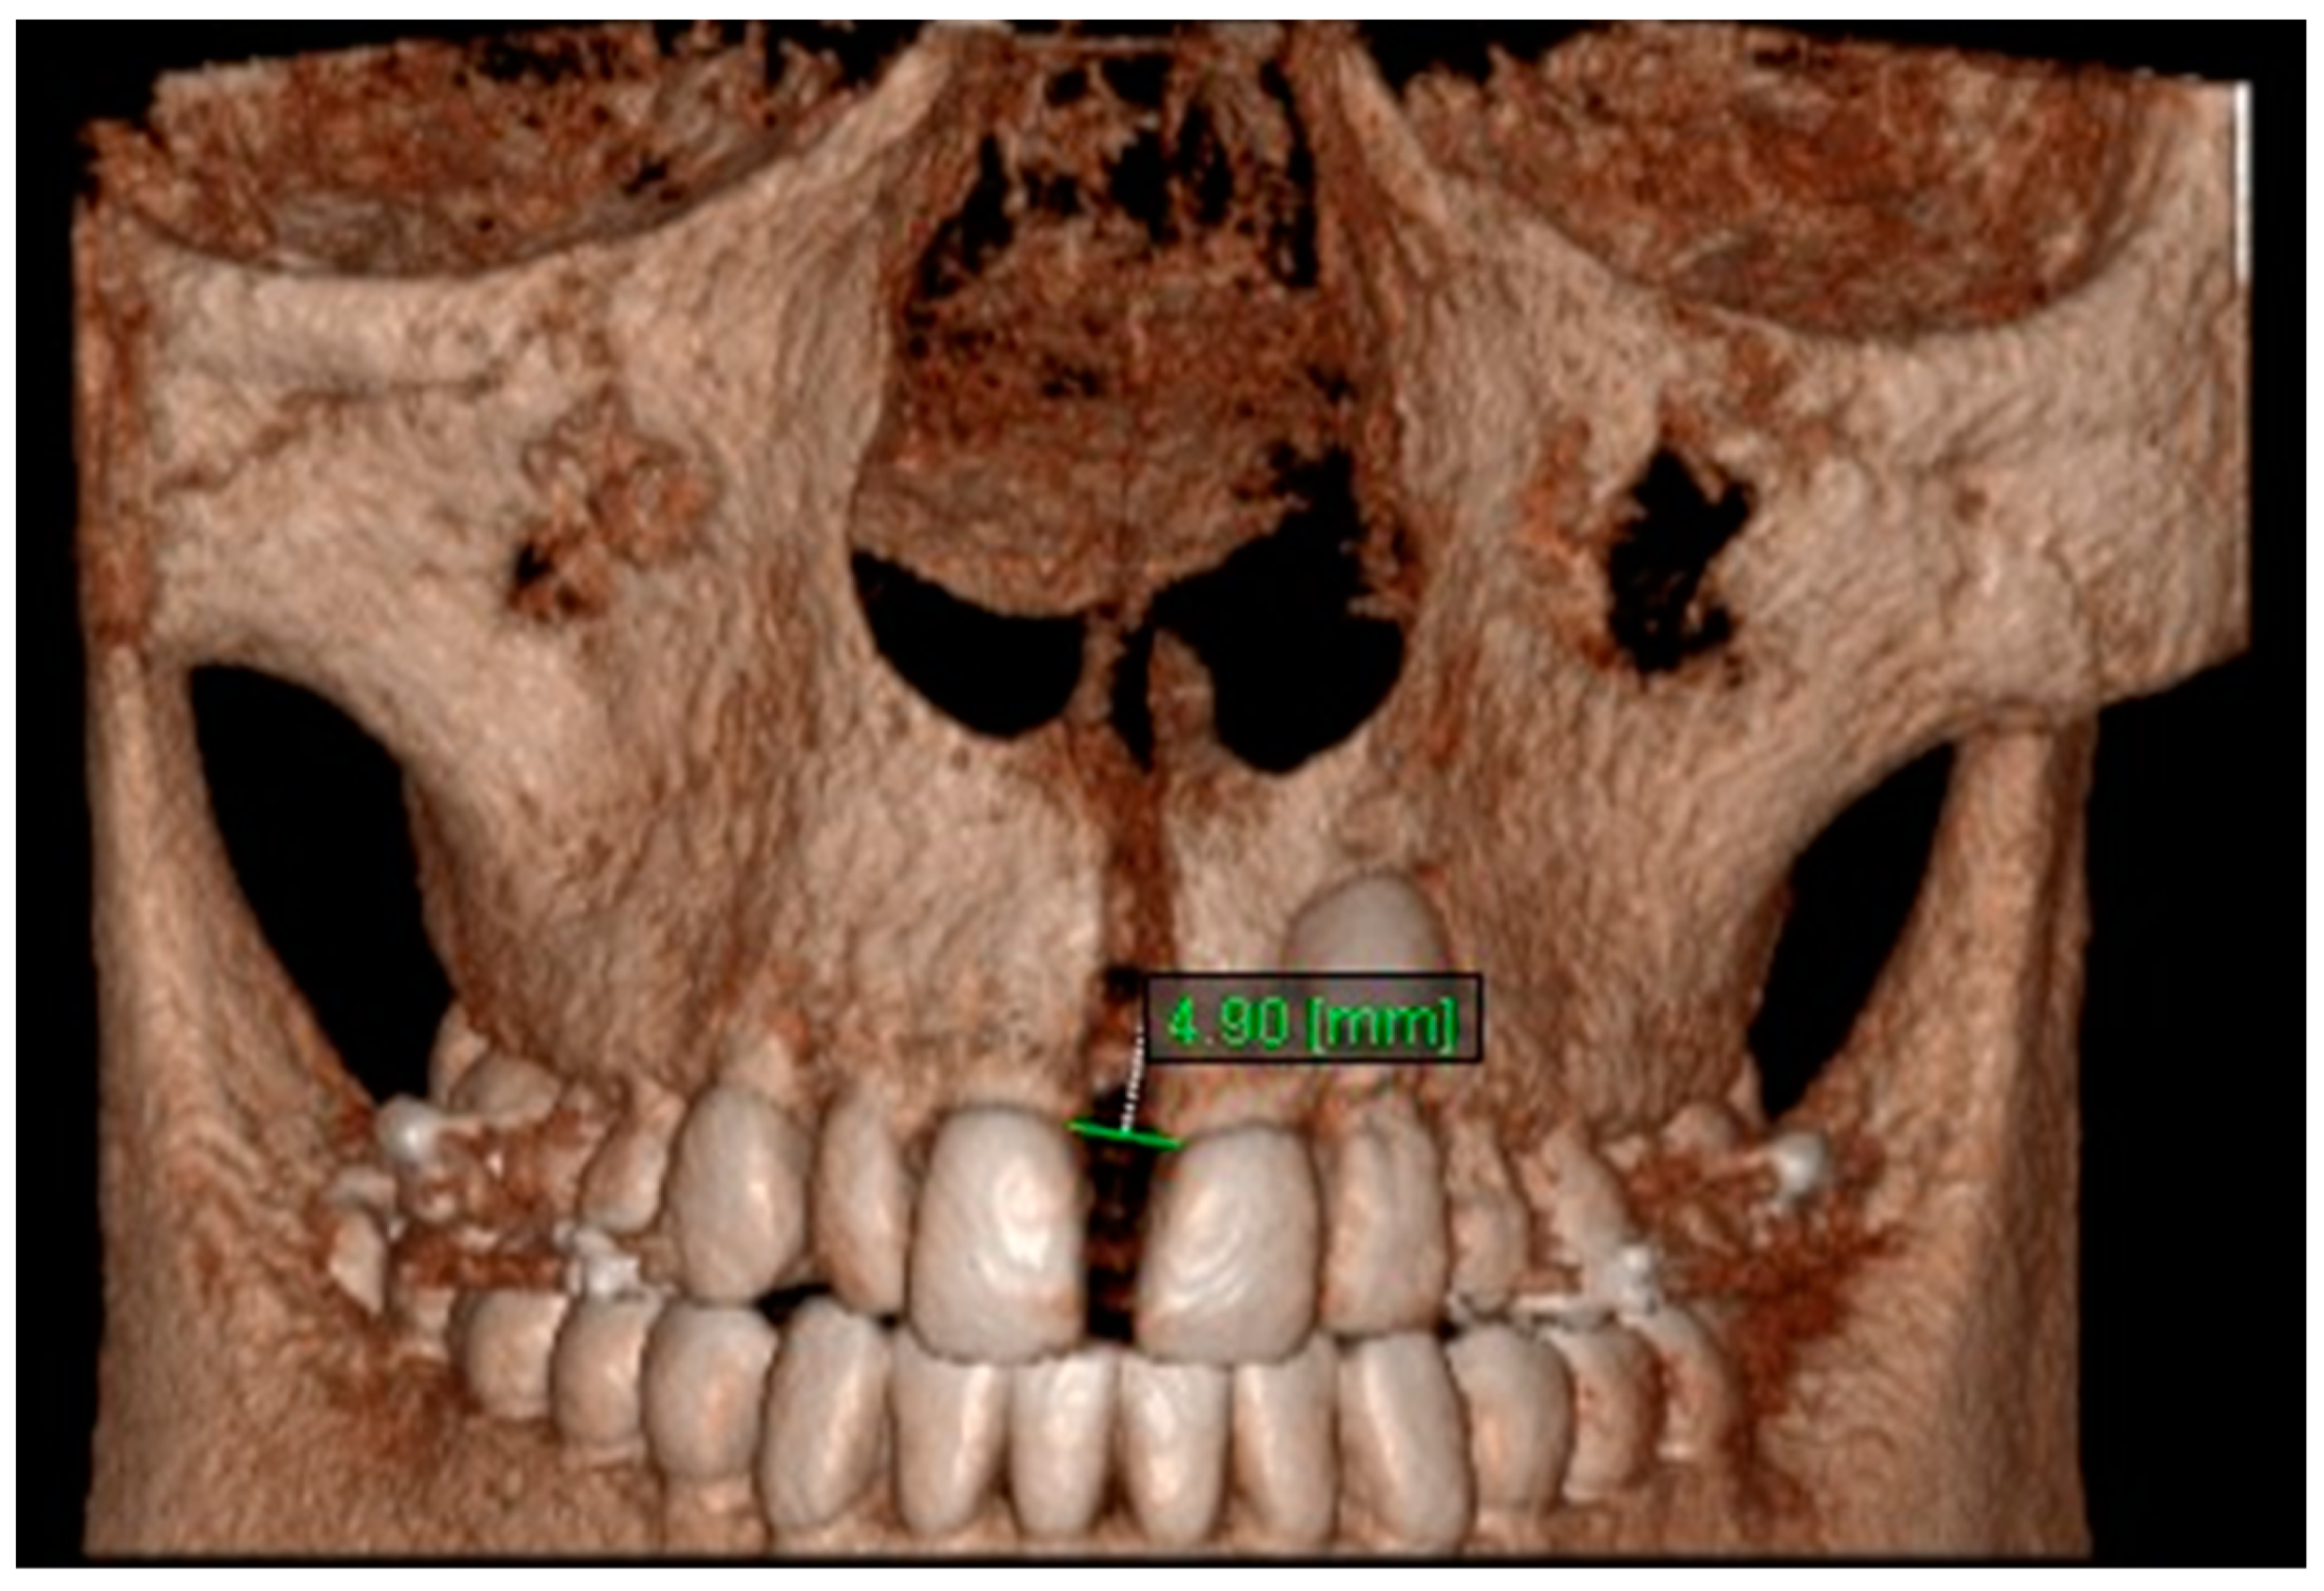

10. Aperture of Midpalatal Suture 10: The distance between the inner points of posterior median palatine suture, bilaterally in posterior nasal spine (PNS) (Figure 12).

Figure 12.

Aperture of Midpalatal Suture 10.

11. Aperture of Midpalatal Suture 11: The distance between the inner points of anterior median palatine suture, bilaterally in the inferior alveolar ridge of central incisors (Figure 13).

Figure 13.

Aperture of Midpalatal Suture 11.

Statistically significant differences were found between the mean value of Apertures of Midpalatal Sutures 10 and 11 between all the time intervals, i.e., between T2–T1, T3–T1 and T3–T2 (p < 0.005). An increase in the mean values of Apertures of Midpalatal Sutures 10 and 11 were observed immediately after the end of RPE (T2–T1). Statistically significant decreases were found 6 months after RPE (T3–T2). The overall (T3–T1) differences between pre-expansion and 6 months after expansion for Apertures of Midpalatal Sutures 10 and 11 were found statistically significantly increased (Table 11 and Table 12).

The results of this study show that the expansion of the maxilla, shown at the aperture of the midpalatal suture, has a triangular pattern. It was found that the amount of increase was greater (a) at the anterior median palatine suture, (b) bilaterally in the inferior alveolar ridge of the central incisors than the posterior, and (c) bilaterally in at posterior nasal spine (PNS). Similar results to our study have shown that the midpalatal suture has a triangle shape, with the triangle’s vertex in the PNS and its base in perspective [1,2,36,37]. According to Da Silva et al. [38], the palatal suture has its largest width in the anterior region and does not have a parallel opening configuration in the axial plane. Additionally, Kartalian et al. [39] found that after RPE, the midpalatal suture separates in a nonparallel manner in response to expansion forces. The maxilla articulates with unpaired bones, which limits the amount of separation. Caldas et al. [40], studying the effect of rapid maxillary expansion on the nasal cavity assessed with cone-beam computed tomography, concluded that there is a great transverse movement and subsequent separation of the nasal conchae from the nasal septum in both the anterior and posterior sections of the inferior portion of the lateral walls of the nasal cavity after RPE.